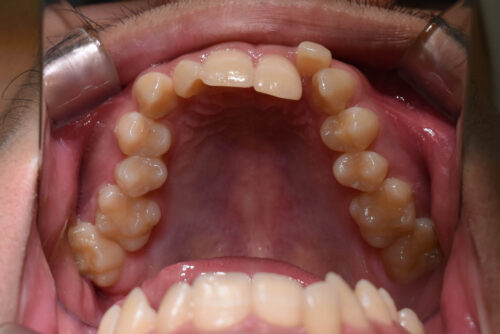

歯のがたつき(叢生)が強く認められ

また下の歯が 全く見えず 過蓋咬合の状態でした。

非抜歯矯正治療で

ワイヤー矯正治療を開始いたしました。